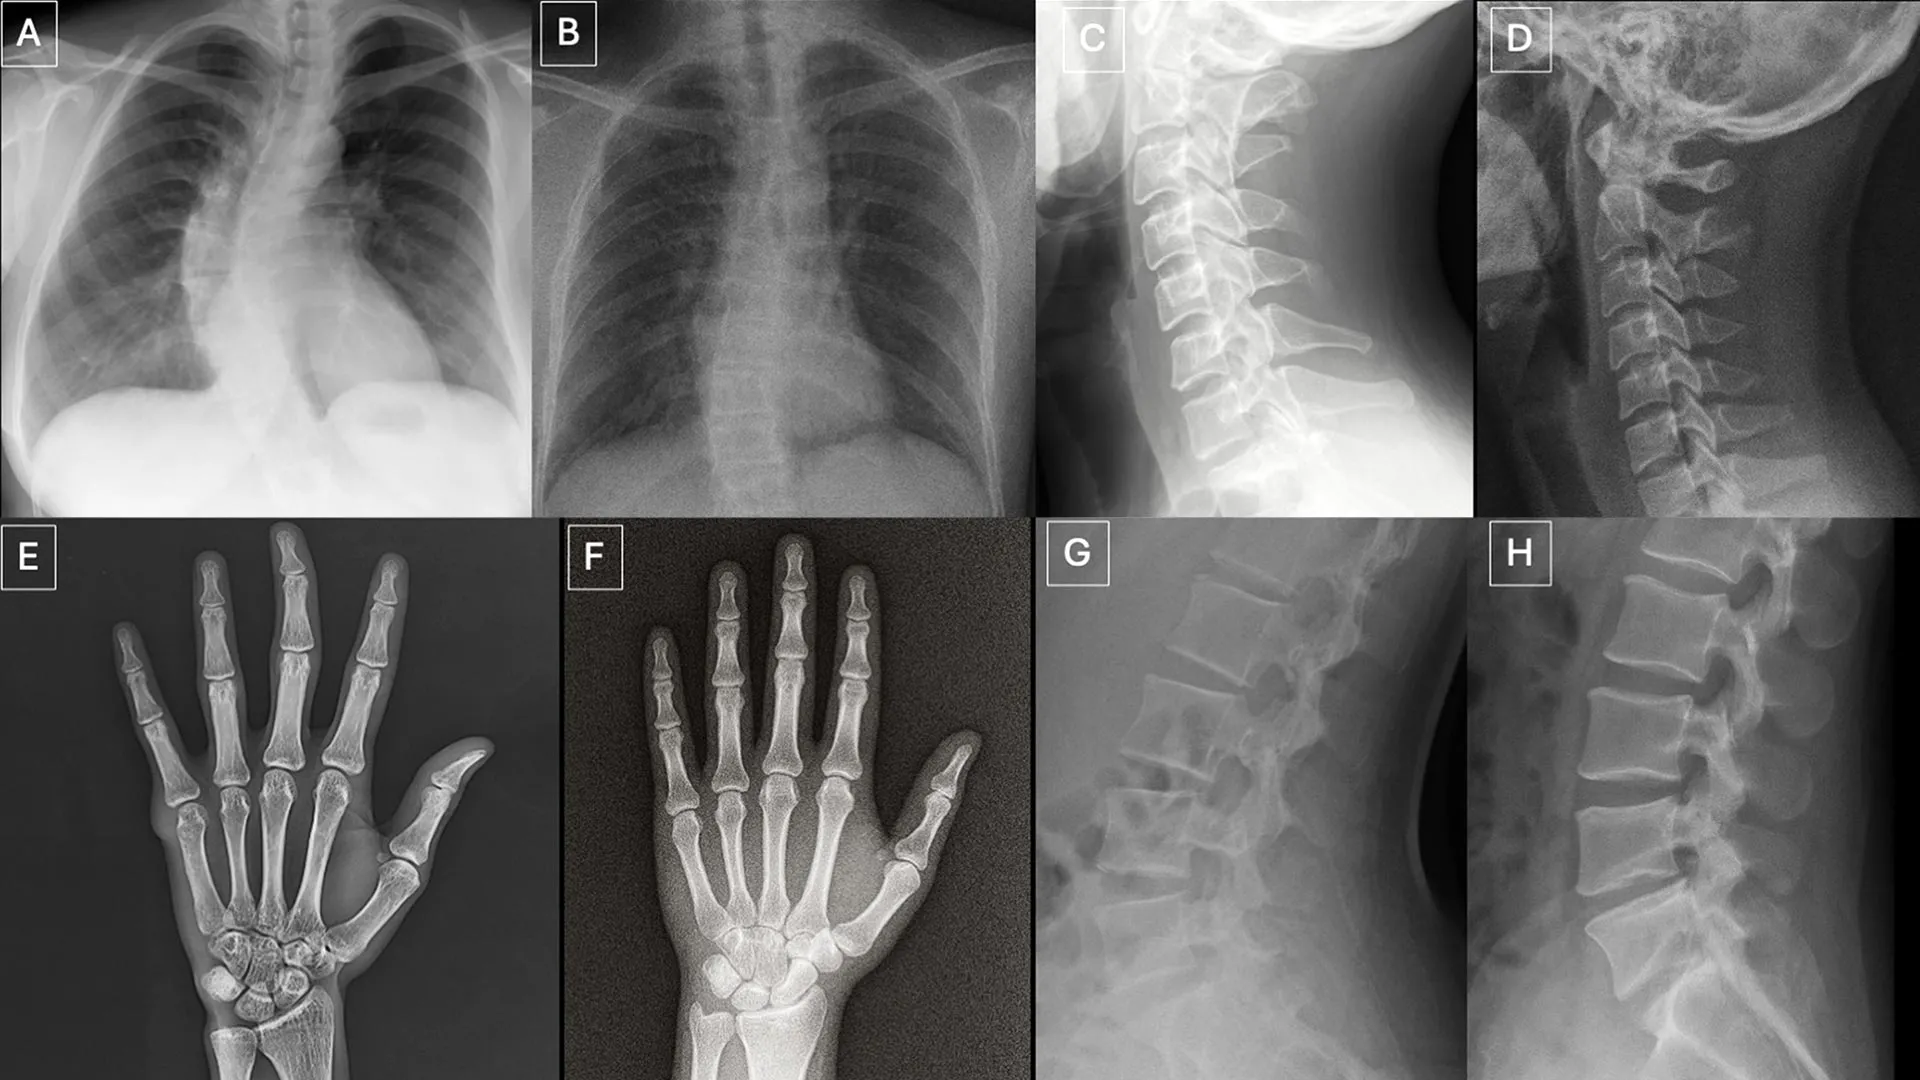

To thoroughly assess detection capabilities, participants were presented with two distinct image cohorts, designed to avoid any overlap or pre-biasing. The initial collection comprised an intricate mixture of authentic X-rays and deepfake images produced by ChatGPT, covering various anatomical regions of the human body. The subsequent set focused specifically on chest X-rays, equally divided between genuine scans and synthetic counterparts generated by RoentGen, an advanced open-source generative AI diffusion model meticulously developed by researchers at Stanford Medicine. This dual approach allowed for a comprehensive evaluation across different generative AI platforms and anatomical focus areas.

The research team meticulously cataloged several recurring visual patterns that served as potential "tells" within the synthetic images. As Dr. Tordjman elucidated, "Deepfake medical images frequently present an appearance that is ‘too perfect’." This uncanny perfection manifests in several ways: bones often appear unnaturally smooth, spines are rendered with an atypical straightness, lung fields might exhibit an exaggerated symmetry, and the intricate patterns of blood vessels could appear excessively uniform. Furthermore, fractures, when present, often possess an unusual cleanliness and consistency, frequently confined to a single side of the bone, lacking the subtle complexities and surrounding tissue reactions typical of real-world trauma. These visual anomalies, while individually subtle, collectively contribute to an overall impression of artificiality that highly attuned observers might eventually learn to recognize.